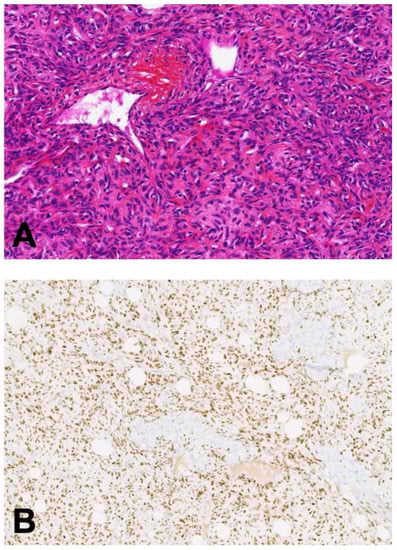

2.3. Biopathology

2.3.3. Tumorigenesis, Pathology, and Molecular Alterations